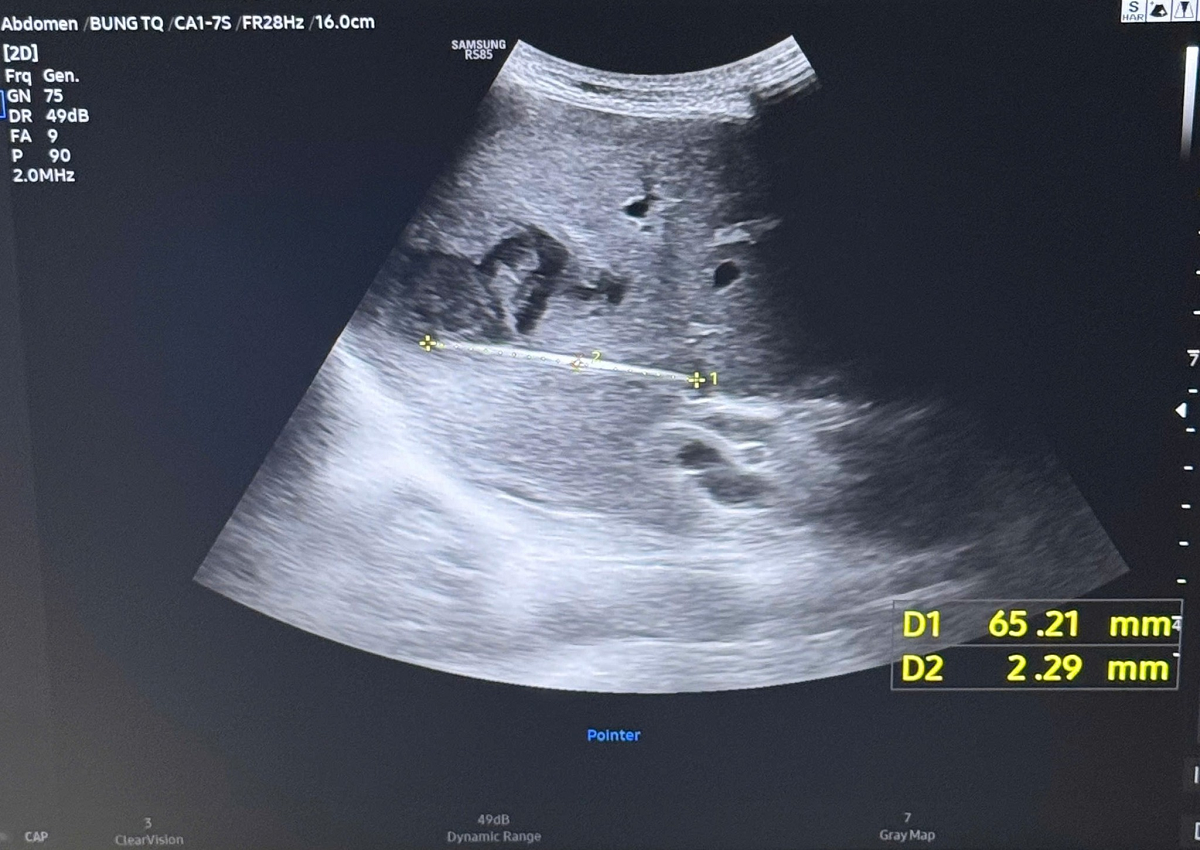

Qua thăm khám ban đầu, bệnh nhân được chỉ định siêu âm ổ bụng và phát hiện có ổ áp-xe gan. Khi tiến hành siêu âm kỹ hơn, ê kíp phát hiện một dị vật cản quang xuyên trong nhu mô gan, chiều dài ước tính khoảng 6-7cm. Ngay sau đó, bệnh nhân được chỉ định chụp cắt lớp vi tính (CT scan) ổ bụng. Kết quả cho thấy có một dị vật dạng que dài nằm hoàn toàn trong nhu mô gan, kèo theo ổ áp xe sâu. Trước nguy cơ biến chứng nặng nếu không điều kịp thời, ê kíp khoa Nội tiêu hóa đã nhanh chóng hội chẩn cùng khoa Ngoại Gan Mật Tụy, thống nhất phương án phẫu thuật lấy dị vật, dẫn lưu ổ áp xe, kết hợp điều trị kháng sinh phù hợp.

Hình ảnh CT Scan ổ bụng của bệnh nhân. Ảnh: BVCC.